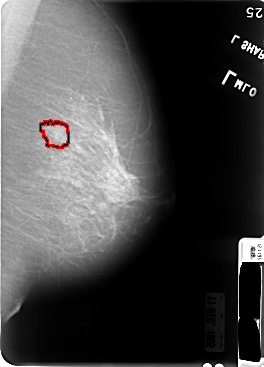

B_3046_1.LEFT_CC

LEFT_CC LINES 4824 PIXELS_PER_LINE 3352 BITS_PER_PIXEL 12 RESOLUTION 50 OVERLAY

FILE: B_3046_1.LEFT_CC.OVERLAY

TOTAL_ABNORMALITIES 1

ABNORMALITY 1

LESION_TYPE MASS SHAPE IRREGULAR MARGINS SPICULATED

ASSESSMENT 4

SUBTLETY 3

PATHOLOGY MALIGNANT

TOTAL_OUTLINES 1

BOUNDARY